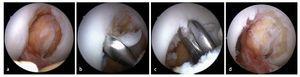

Fig. 6 La fase intraarticular de la intervención empieza con un diagnóstico artroscópico en el que se inspeccionan todos los compartimentos en cuanto a lesiones del cartílago y del menisco. Las lesiones de menisco asociadas se refijarán o reseccionarán. Ante lesiones del menisco de cuarto grado se llevará a cabo una microfracturación. En caso de inestabilidades crónicas, los osteofitos pueden estrechar la fosa intercondílea (a). En este caso, la cirugía de reemplazo del ligamento cruzado se inicia con una resección de osteofitos (intervención de la fosa intercondílea). Esta intervención se puede llevar a cabo con una cuchara afilada (b), una pinza gubia (c) o una fresa de bola. d) Fosa intercondílea ensanchada.